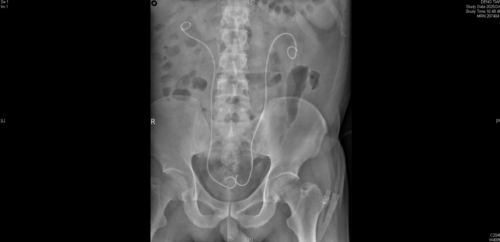

术后复查,双侧输尿管支架管留置,梗阻解除